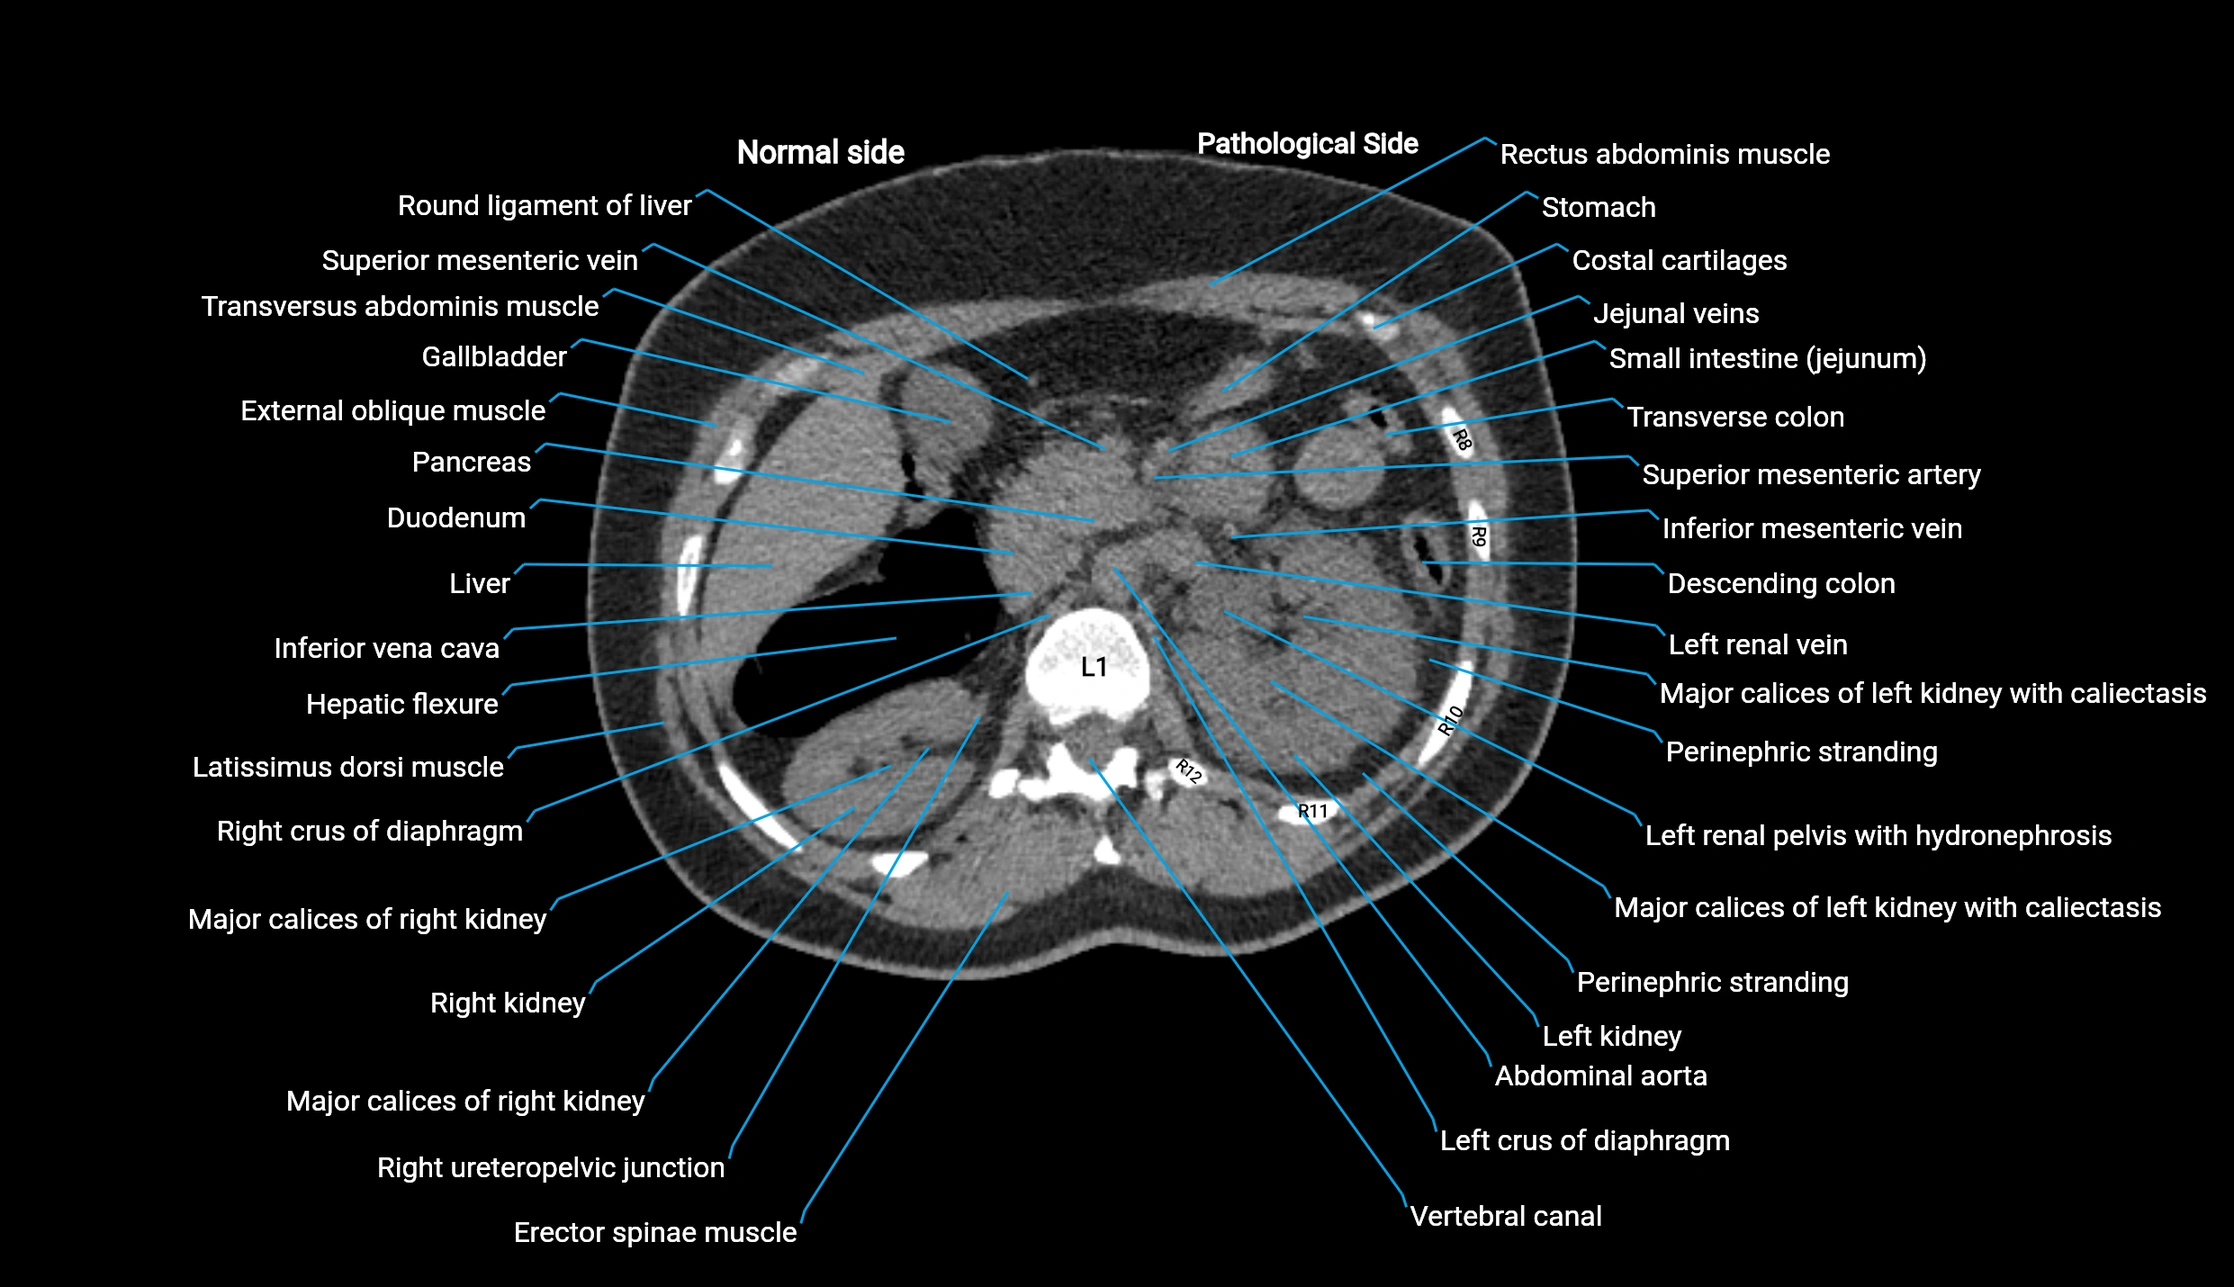

CT Appearance

Post-Contrast CT (Contrast-Enhanced CT):

• Portal venous phase:

• Anterior right portal branch enhances intensely and homogeneously

• Clearly separates from posterior branch

• Branching pattern to segments V and VIII sharply defined

• Arterial phase:

• Slight enhancement but less conspicuous than in portal phase

• Coronal and sagittal reconstructions:

• Optimal visualization of segmental bifurcation

• Used for preoperative liver mapping

• CT liver segmentation:

• RAPV acts as the principal boundary landmark for dividing anterior vs. posterior right hepatic segments